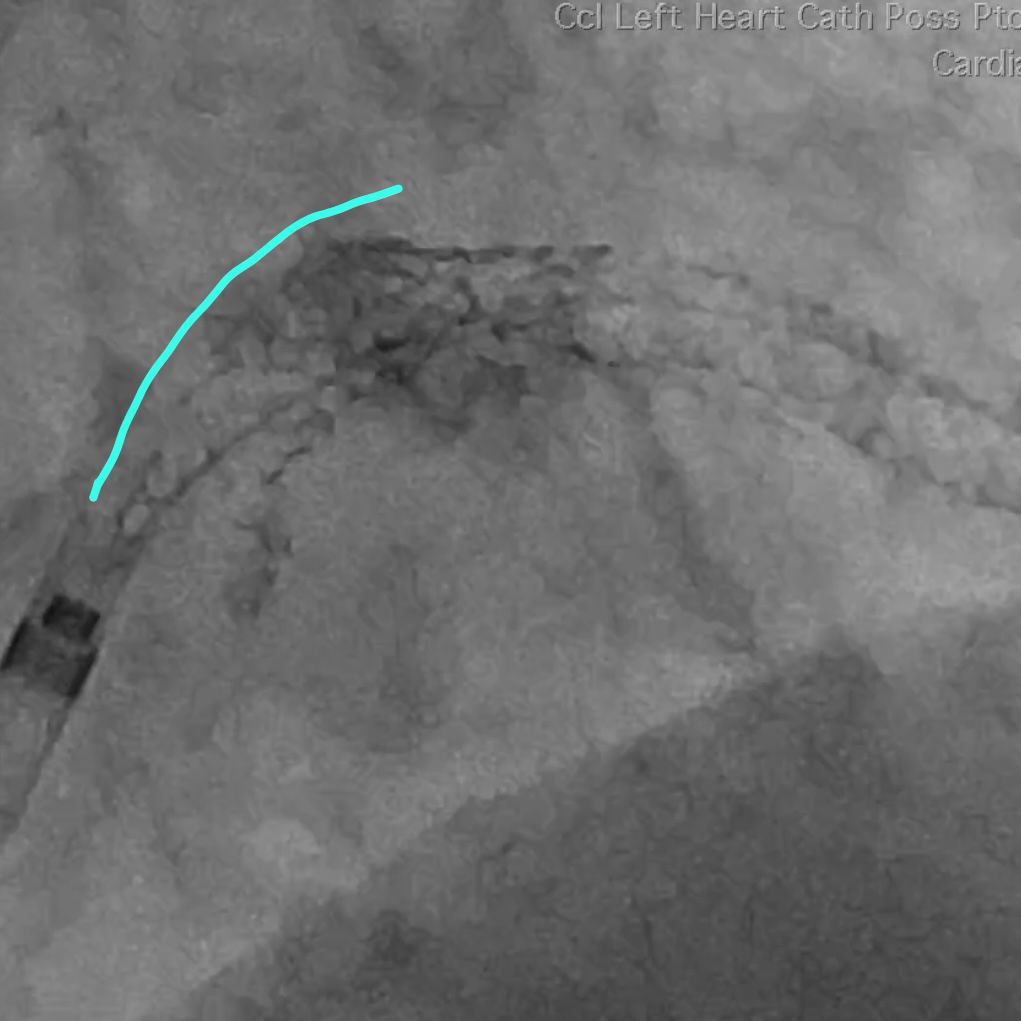

This is after our aggressive POT. Note the smoother upper curvature.